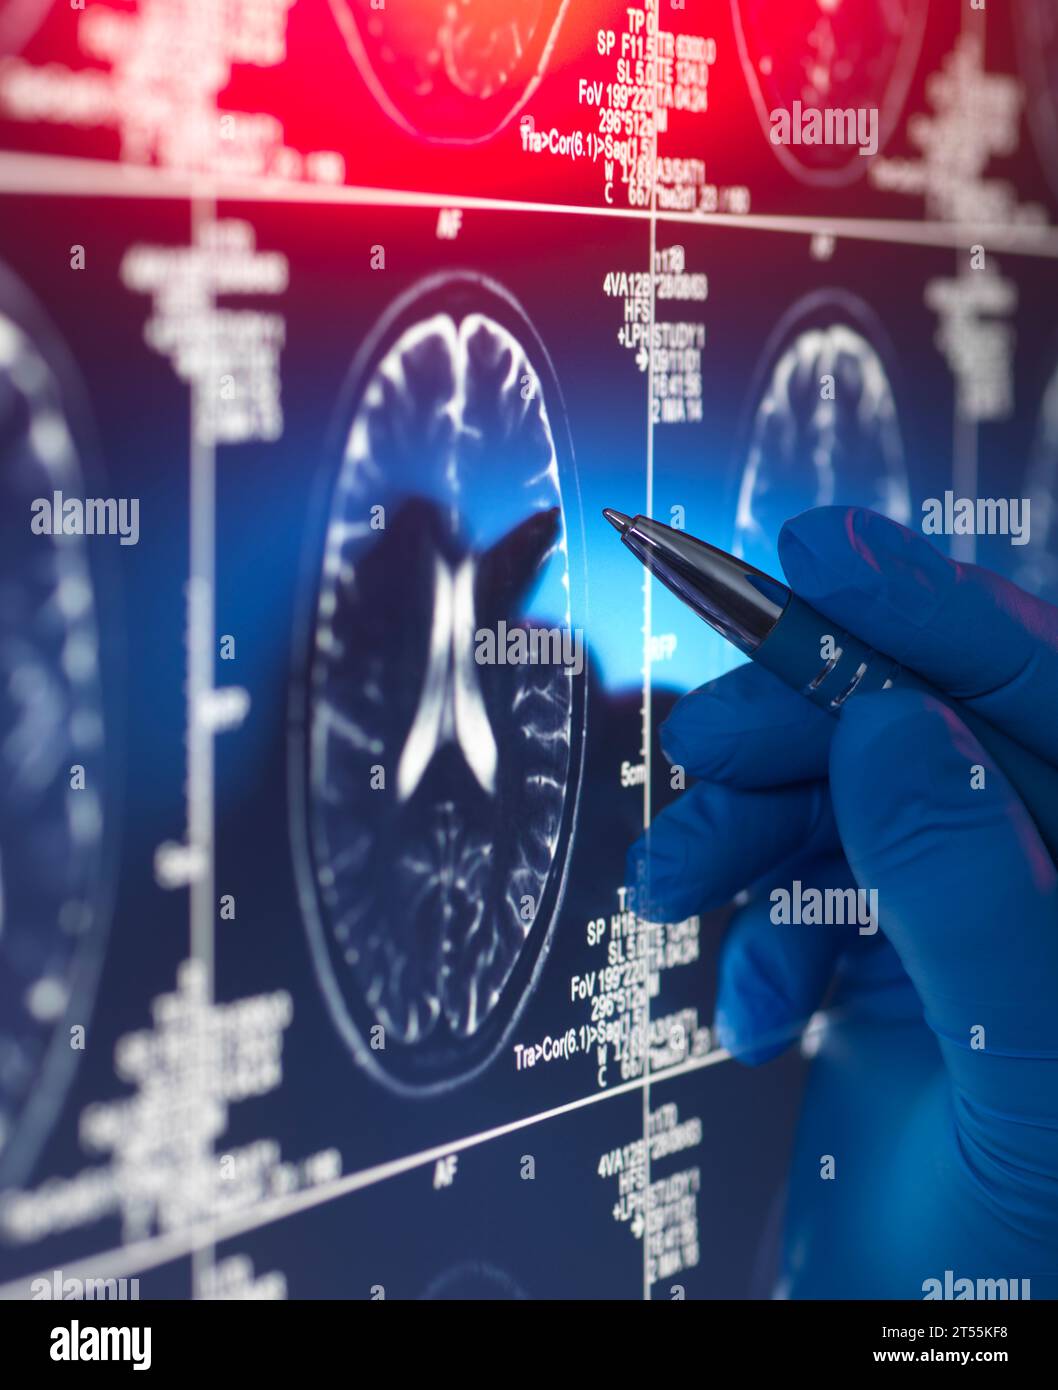

Doctor viewing a patients brain scan on screen Stock Photohttps://www.alamy.com/image-license-details/?v=1https://www.alamy.com/doctor-viewing-a-patients-brain-scan-on-screen-image571140508.html

Doctor viewing a patients brain scan on screen Stock Photohttps://www.alamy.com/image-license-details/?v=1https://www.alamy.com/doctor-viewing-a-patients-brain-scan-on-screen-image571140508.htmlRF2T55KF8–Doctor viewing a patients brain scan on screen